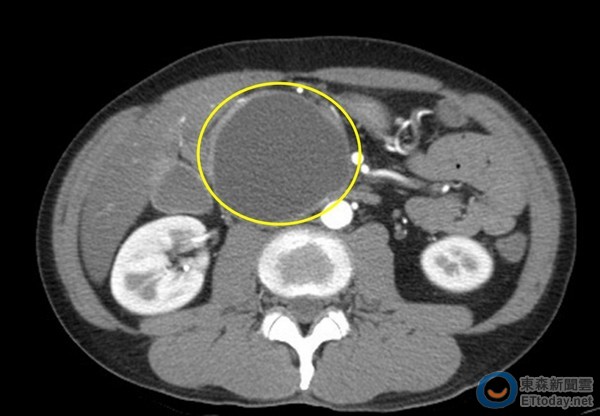

▲電腦斷層影像顯示假性囊腫位置(黃圈處)。(圖/台北慈濟醫院提供)

45歲的黃先生長期酗酒,某天腹部劇痛,就醫診斷為急性胰臟炎,胰臟有還6公分大的假性囊腫,已壓迫到十二指腸,時常感覺腹脹,吃一點東西就脹氣,更在三個月內暴瘦10公斤。台北慈濟醫院以內視鏡超音波技術,在十二指腸和囊腫之間置放支架,引流囊腫液體到腸道,再排泄到體外。過程中只需輕度麻醉,也免除傳統剖腹手術器官沾黏的風險,無傷口、恢復快,術後3天即順利出院。